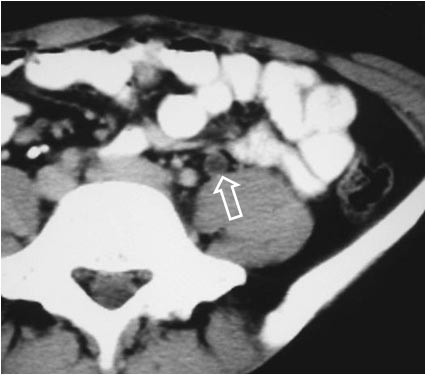

Otro ejemplo de vejiga de pera de origen diferente. Dos cortes contiguos de TC pélvico en un paciente con linfoma muestra el signo debido a la compresión por las masas adenopáticas bilaterales (flechas).